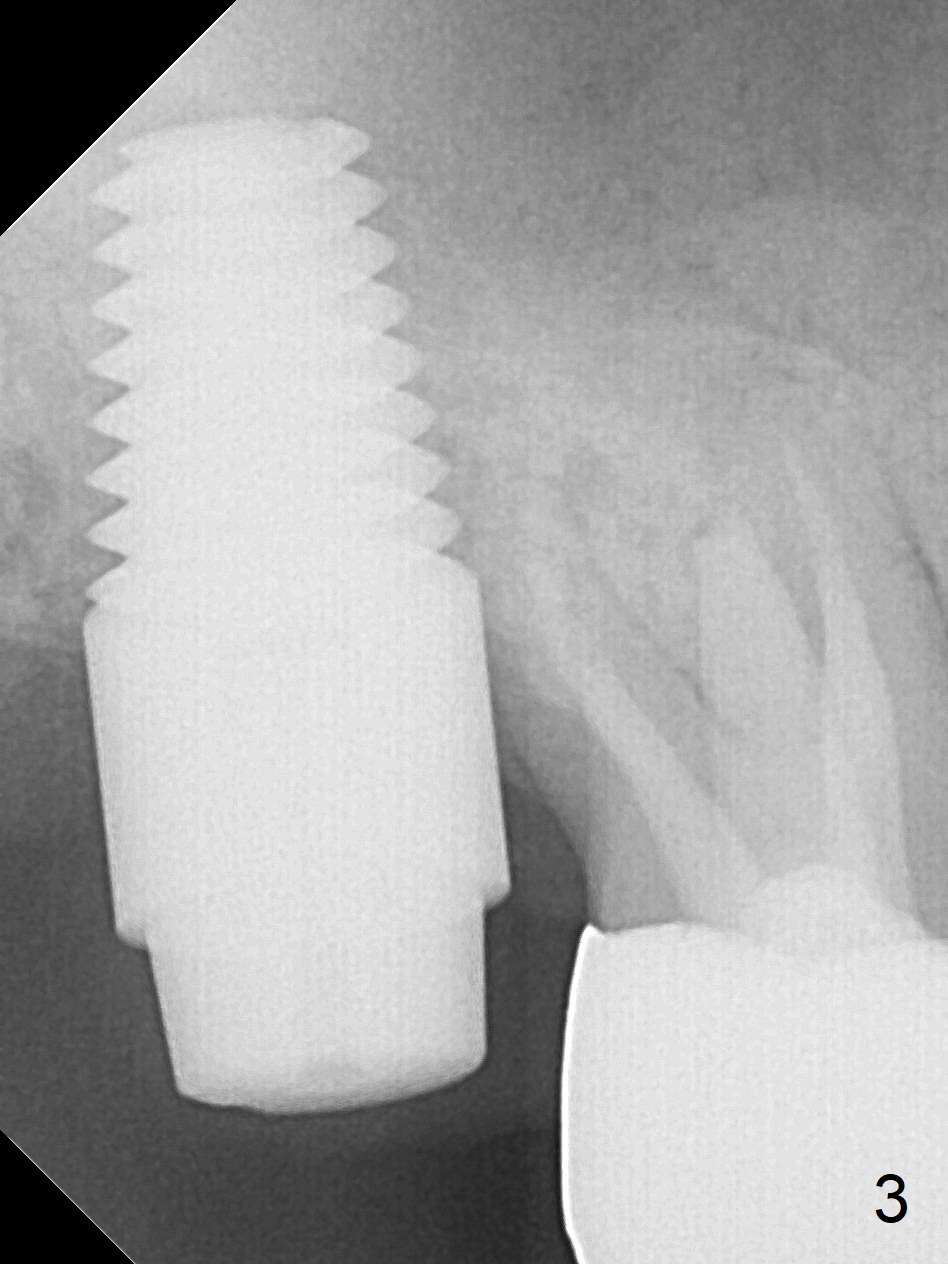

7 mm Fixture

The tooth #2 is found to have fracture at extraction. The buccal (B) socket (*) has more resorption than the palatal (P) one (Fig. A (S: sinus). The buccal plate is also lower. Osteotomy is initiated in the buccal slope of the septum with Magic Expanders (ME, 3-4.8 mm, Fig. B (red)), followed by Tatum tapered tap drills (Fig. C (green), Fig.1 (5x17 mm)). As the diameter of ME and tap increases, the osteotomy is shifting buccally due to bone height discrepancy (Fig. C). A Lindamann bur is used to remove the palatal bone (Fig. D (pink) and move the osteotomy palatally (Fig. E). The coronal end of 7x14 mm tissue-level fixture (Fig.2) tilts buccally (Fig. F purple). Insertion torque is 35/40 Ncm. Prior to implantation, a piece of PRF membrane and allograft are pushed into the sinus. A 6x3 mm abutment (Fig.2) is immediately placed to keep an immediate provisional, bone graft and collagen membrane in place. Bone seems to have grown into the space between the implant threads 5.5 months postop (Fig.3). There is no bone loss 2 years 2 months post cementation (Fig.4).